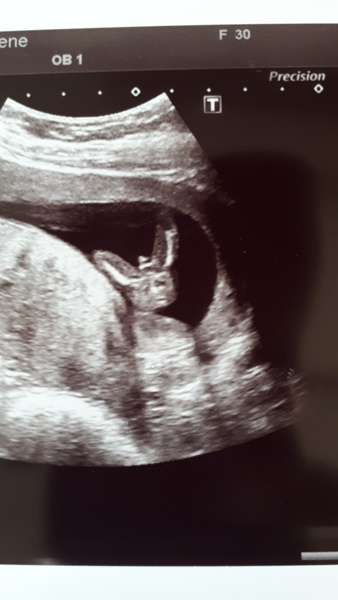

lovebeingmum9 · 03/06/2019 09:18

heres scan pic

@lovebeingmum9 that's lovely how you told the kids 😍 they're gonna get a little brother or sister for Christmas 😊

Gorgeous little scan picture... although you can sort of see what looks like boy bits... or is that just me

Hi and Thanks @december2019 yeah they will be over the moon either way but I've told them it's most likely a boy....Will post my inbetween the legs scan pic,me and the sonographer had a giggle as could see the boy parts! we've already got 2 boys and their 12wk scans was just as telling! lol